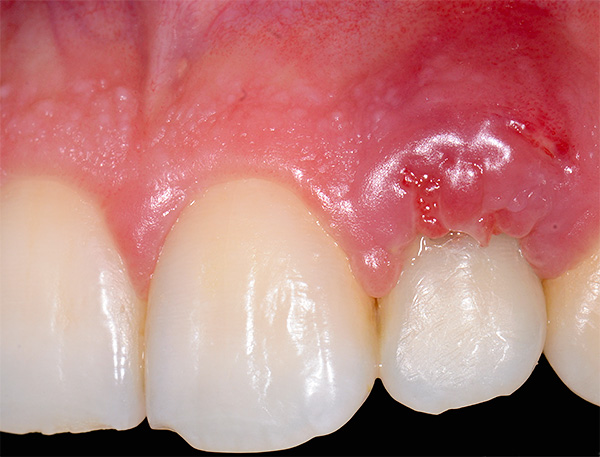

Talvez também seja importante mencionar a divergência de suturas, frequentemente aplicada à ferida após o implante. A foto abaixo mostra um exemplo do estado normal das suturas imediatamente após a cirurgia:

A divergência das suturas, como complicação, quase nunca é sinal de implantes dentários mal sucedidos, pois caracterizam mais o resultado do comportamento da própria pessoa. As violações podem ser muito diferentes: desde a não observância dos princípios de higiene bucal e ignorando as recomendações do médico, até o "toque" não autorizado na cavidade oral com dedos, palitos de dente, etc., o que leva a danos mecânicos nas suturas ou contribui para o início do processo inflamatório. Isso provoca a divergência de costuras no futuro.